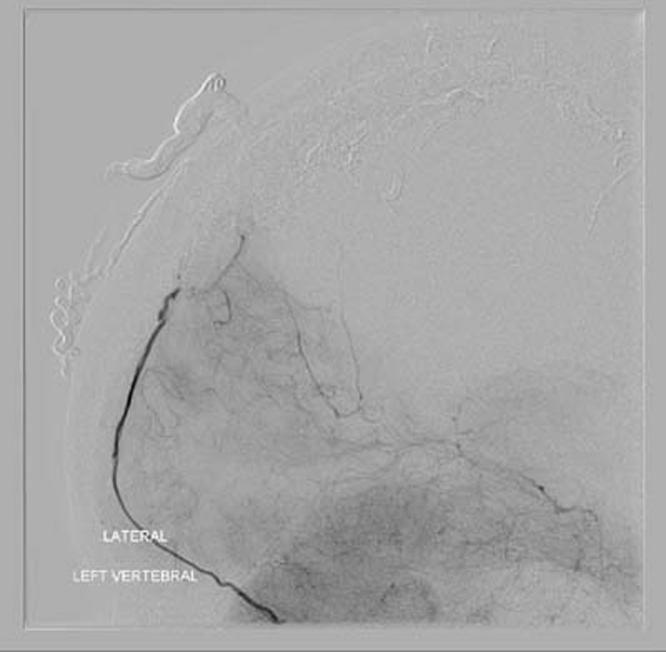

Unusual Presentation of a Dural Arteriovenous Fistula of the Superior Sagittal Sinus and Single Modality Therapy with Onyx.

Superior sagittal sinus (SSS) dural arteriovenous fistulas (DAVF) are rare and present unique challenges to treatment. Complex, often bilateral, arterial supply and involvement of large volumes of eloquent cortical venous drainage may necessitate multimodality therapy. We report a case of a DAVF of the SSS in a patient who presented uniquely with increasing dizziness and disequilibrium who was treated with a single modality, endovascular embolization with ethyl vinyl alcohol co-polymer (Onyx, EV3, Irvine, CA). The patient underwent staged embolization in 2 sessions with no complications. An angiographic cure was achieved and the patient's symptoms were ameliorated. Single modality therapy with endovascular embolization of a SSS DAVF can be achieved. Careful attention to technique during embolization with Onyx is required, but complete obliteration is possible without the need for adjunctive surgical resection.

上矢状窦(SSS)硬脑膜动静脉瘘(DAVF)较为罕见,治疗面临独特挑战。复杂且常为双侧的动脉供血以及大量功能区皮质静脉引流受累,可能需要多模式治疗。我们报告1例SSS的DAVF患者,该患者以头晕和平衡失调进行性加重为独特表现,接受了单一模式治疗,即使用乙烯 - 乙烯醇共聚物(Onyx,EV3,加利福尼亚州欧文市)进行血管内栓塞治疗。患者分2期进行栓塞,无并发症。实现了血管造影治愈,患者症状得到改善。SSS的DAVF采用血管内栓塞单一模式治疗是可行的。使用Onyx栓塞时需要密切关注技术,但无需辅助手术切除即可实现完全闭塞。